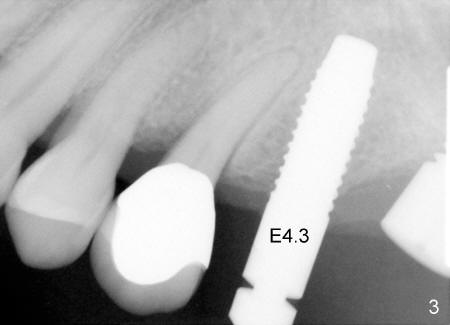

Effort was exerted to correct the trajectory of bone expanders using the crown of the neighboring tooth as a guide. There was not much improvement (Fig.3 E4.3: bone expander 4.3).